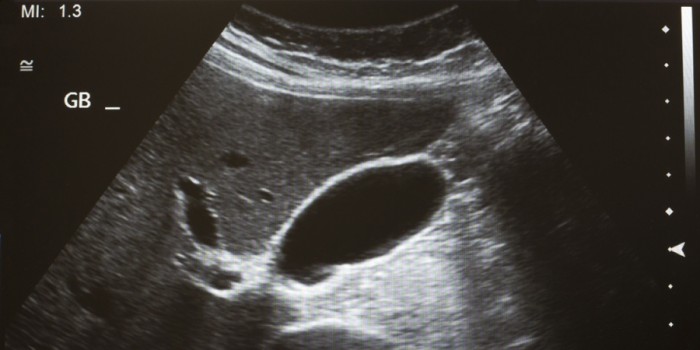

Weinig huisartsen maken zelf echo’s, maar na een cursus echoscopie blijken ze eenvoudige diagnoses zelf te kunnen stellen. De beoordeling van getrainde huisartsen komt overeen met die van een specialist. Dat blijkt uit Scandinavisch onderzoek.

Vier huisartsen en een huisarts-in-opleiding volgden een echoscopiecursus die bestond uit drie onderdelen: e-learning, twee onderwijsdagen en een feedbacksessie. Vervolgens pasten de cursisten hun vaardigheden toe in de praktijk. Ze verrichtten echo’s met de indicatie galstenen, ascites, verwijde aorta abdominalis (meer dan 5 cm), intra-uteriene zwangerschap of zwangerschapsduur. Een radioloog of gynaecoloog herhaalde de echo, blind voor de eerste echo-uitslag. De uitkomst van het onderzoek was de interbeoordelaarsovereenstemming.

In totaal verrichtten de huisartsen 188 echo’s bij 104 patiënten. Gemiddeld duurde een echo zes minuten. De interbeoordelaarsovereenstemming was bijna perfect, de kappacoëfficiënt was 0,93. Voor ascites, verwijde aorta en intra-uteriene zwangerschap was er zelfs volledige overeenstemming met de specialist (kappacoëfficiënt 1,0).